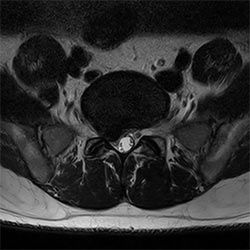

In a society where reimbursements are declining and chronic conditions lead to increased MR procedures and longer waiting times, there is ever increasing pressure on the radiology department. Today, further attempts to accelerate, compromise image quality or are limited to a narrow range of scans. Therefore, to meet the increased demand for productivity, a technology break-through in acceleration is still required. Leveraging our long standing leadership position in speed (i.e. SENSE), Philips brings compressed SENSE, a breakthrough in productivity.

Learn more about the main principles of Compressed SENSE and how it introduces a paradigm shift in productivity, how Compressed SENSE was designed around image quality, and how it advances productivity for clinical MR imaging.

Read about the experiences from Kantonsspital Winterthur (Switzerland) who experienced Compressed SENSE to be a simple yet powerful way to accelerate MRI scanning for different contrast types and sequences, in 2D as well as 3D.